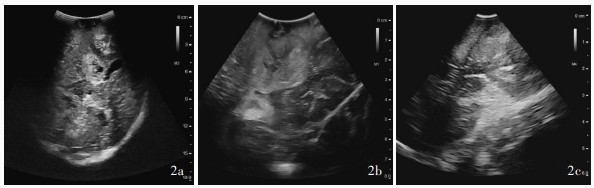

Šteňo A, Buvala J, Šteňo J. Large residual pilocytic astrocytoma after failed ultrasound-guided resection: intraoperative ultrasound limitations require special attention. World Neurosurg, 2021, 150: 140- 143.

doi: 10.1016/j.wneu.2021.03.138